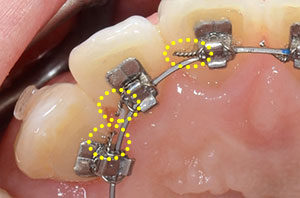

<従来の装置>

上の写真のように、歯の裏側につけた装置を結紮しています。